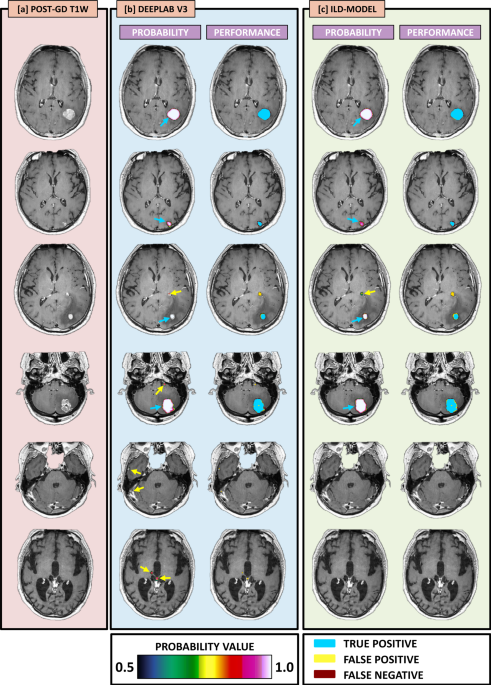

In our paper entitled ‘Handling Missing MRI Sequences in Deep Learning Segmentation of Brain Metastases: A Multi-Center Study’, which is published in npj – Digital Medicine, we aimed to improve the robustness and generalizability of our segmentation network by utilizing an input-level dropout (ILD) model. A diagram showing the ILD-pipeline, as well as four example cases with resulting AI-based segmentations, is shown in Figure 1. In this neural network, a dropout layer at the input-level is trained on the full set of four distinct MRI sequences, as well as every possible subset of the MRI sequences. This way, our ILD-model can allow segmentation even in the setting where individual MRI sequences are missing. This enabled us to generalize our deep learning segmentation model for use in multiple different imaging sites.  Our model showed high performance and accuracy, equivalent to that of expert neuroradiologists, in a separate cohort of patients with different scanners and imaging protocols.

Figure 1: Diagram showing the neural network pipeline used in this study. The left column shows MRI data from four representative example cases. The MRI data is fed into the input-level dropout (ILD) model shown in the middle column. The right column shows the predicted segmentation as likelihood-maps overlayed the input MRI-data. The voxel-wise likelihood of being within a metastatic lesion is indicated by the color-bar.